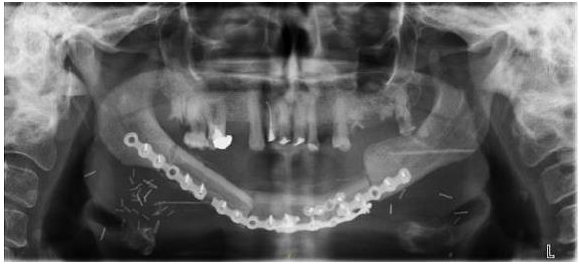

The first oral complaints appeared in June 2014; the patient reported mandibulary pain on the right side. Examination showed an abscess on 44 (right first pre-molar), which was extracted in November 2014. Denosumab was discontinued. Healing was very slow and incomplete. In April 2015, an external fistula with purulent discharge appeared at the inferior portion of the chin; intra-oral examination showed exposed mandibulary bone and loose teeth with an overall bad oral hygiene. Panoramic X-ray showed mandibulary Osteonecrosis involving both sides of the mandibulary symphysis (left 34-35) and right (45-46) with a fracture of the jaw (Figure 1). Therapy with amoxicillin (orally) and H2O2 rinses was started. In July 2015, the situation was unchanged but a large abscess had appeared under the chin; a surgical drainage was undertaken; amoxicillin and H2O2 rinses were continued. In October 2015, the situation was unchanged and the same therapy was continued; at the same time the patient was receiving everolimus, in addition to exemestane and extensive aphtosis was successfully treated with low level laser therapy. Because the stage III mandibulary Osteonecrosis was still progressing with extensive bone necrosis and multiple external fistulae, in spite of continuing therapy with various antibiotics, the decision to perform a wide resection of the lesions was taken in April 2016, following extensive discussion between the patient, the oncologist and the oral surgeon.

Figure 1 Mandibular osteonecrosis involving both sides of the mandibular symphysis (March 30, 2015).